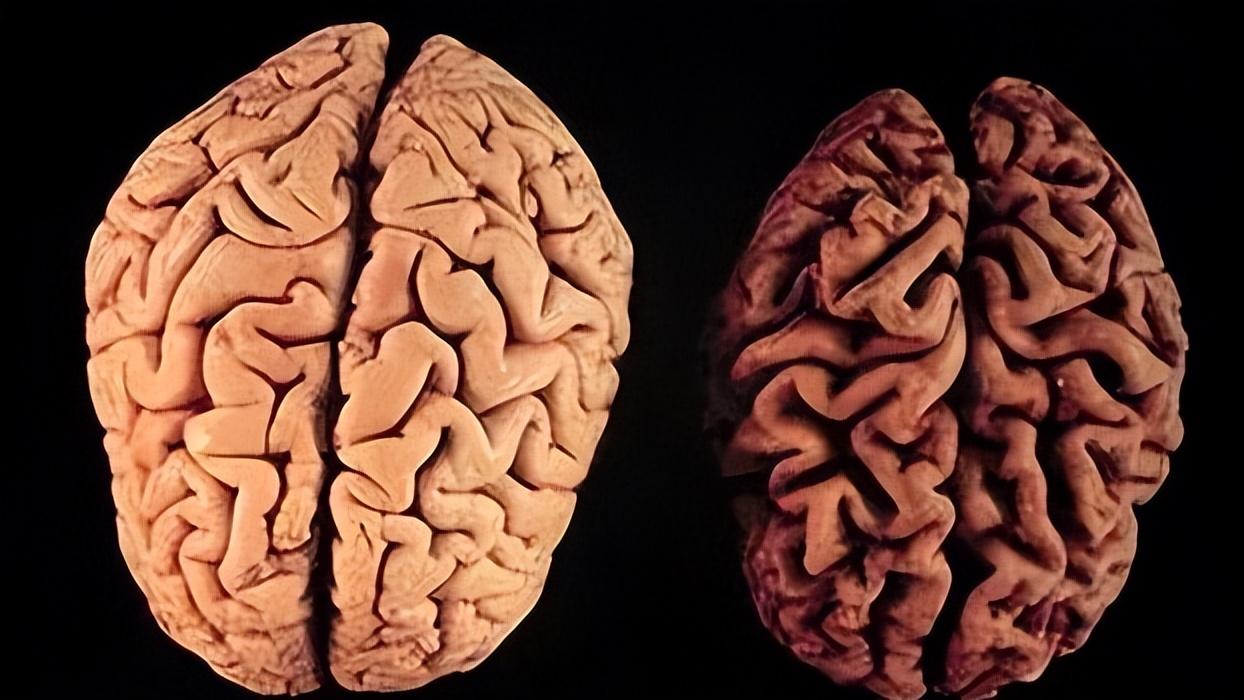

脑萎缩,单单是这三个字可能就会让人不寒而栗。其实见字名义,萎缩就是体积缩小,脑萎缩就是大脑变小了。

大脑外观可能看起来像个核桃仁,但它是上亿个神经细胞以及为这些神经细胞提供营养物质的神经胶质细胞和神经纤维等。人生就是出生后长大,再到青年和中年,最后逐渐走向老年,是一个抛物线一样的发展过程。

大脑亦是如此,到了老年时,它也会逐渐衰老和退化。因此大脑中各种各样的脑细胞就会逐渐减少。过往统计研究,当我们70岁时,这些脑细胞已经至少减少了30%。所以内容物减少了,那么质量和体积减少也是正常的。这就是生理性脑萎缩,一般CT片子下都是脑回变窄,脑沟加深等字眼。

所以生理性脑萎缩是完全不可抗和不可逆的正常人体发展现象和轨迹。当然,随着脑细胞的减少,大脑功能势必会下降,因此我们老了之后认知、记忆等功能也会逐渐减退。